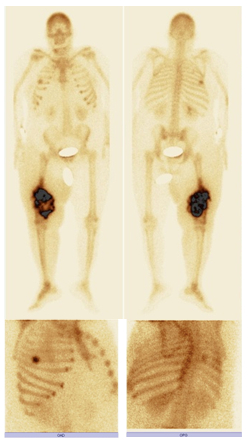

The patient was then addressed to our nuclear medicine department for a mapping of her bone lesions. Bone scintigraphy showed, in addition to the primary tumor known at the 2/3 of the right femur, a second localization to the middle arc of the 5th right rib (Figure 2).

Figure 2 99mTc-HMDP: bone scan showing, beside the primary in the 2/3 of right femur, a second localization at the middle arc of the 5th right rib.

In this case report, a 55 year old female with uncontrolled acromegaly was diagnosed with osteosarcoma in her right femur and the middle arc of the 5th right rib. Interestingly, the patient has no known risk factors for osteosarcoma which may indicate an association between this cancer and acromegaly except her high GH and IGF-1 levels that could be a risk factor for the development of her aggressive bone tumor.